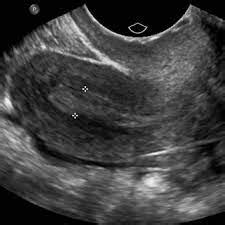

- Ecografie transvaginală: Aceasta este o metodă principală de diagnosticare. Ecografia ajută la verificarea stării endometrului, a ovarelor și a uterului, putând identifica eventuale anomalii sau probleme.